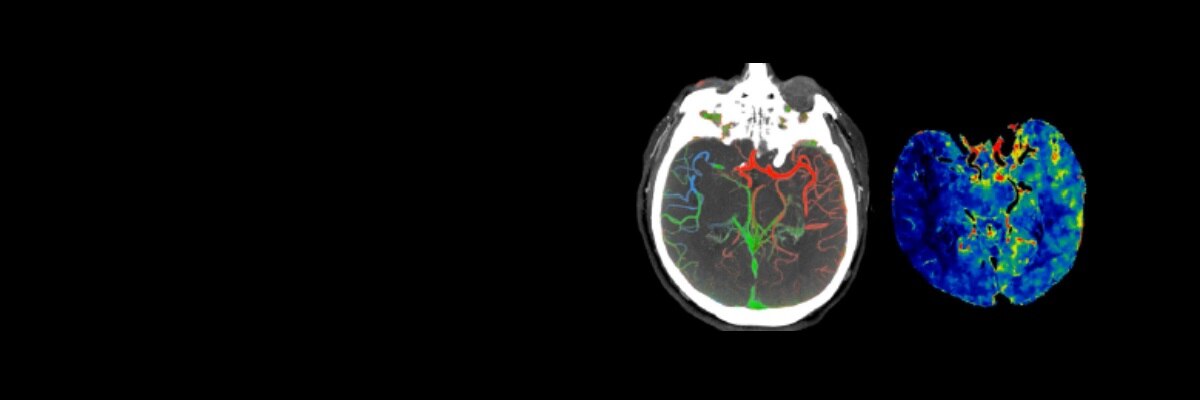

Un patient susceptible d'avoir souffert d'un AIT ou d'un AVC subit un examen général et neurologique suivi d'une imagerie cérébrale diagnostique, effectuée immédiatement à son arrivée afin qu'un traitement puisse être entrepris rapidement. 3 Un système d'acquisition optimal associé à des applications de flux de travail et à des protocoles conçus pour l'AVC permettent d'établir un diagnostic précis et rapide afin d'optimiser les résultats pour le patient.

Gamme de systèmes CT Revolution

Le système Revolution est capable d'acquérir une neuro perfusion et une angiographie (CTA) du cerveau en un seul examen pour une évaluation fonctionnelle et anatomique complète. Pour en savoir plus

Application FastStroke CT

Simplifie et organise les images CT pour une évaluation rapide des patients souffrant d'un AVC. Pour en savoir plus